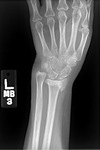

Wrist fractures

Type A extra-articular fracture of the distal radius: lateral view

From the collection of Dr Chaitanya S. Mudgal